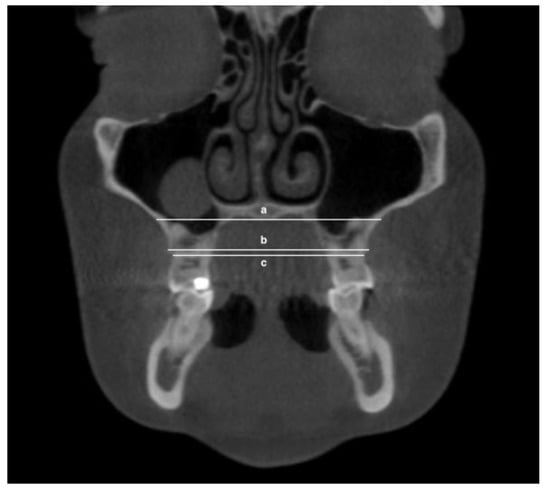

- Maxillary inter-lingual bone widths: from the right to the left points at the level of alveolar crest and furcation (Figure 2)